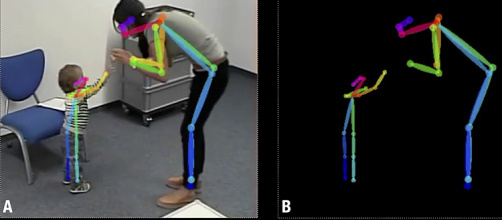

Détecter l’autisme précocement par vidéo